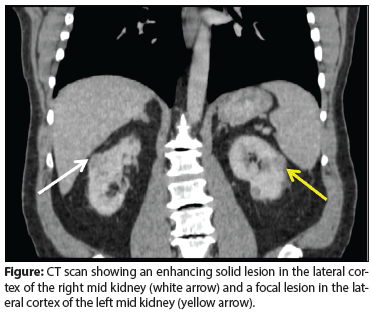

Figure: CT scan showing an enhancing solid lesion in the lateral cortex of the right mid kidney (white arrow) and a focal lesion in the lateral cortex of the left mid kidney (yellow arrow).

A CT scan revealed bilateral renal masses. On the right side, a mass was discovered in the lateral cortex of the mid kidney that measured approximately 2.7 × 1.8 cm in the cross-section and 3.2 cm in length; it appeared to be solid and heterogeneously enhanced (Figure). On the left side, a focal lesion in the lateral cortex of the mid kidney, measuring approximately 2.2 × 1.5 cm in the maximal cross-section and 2 cm in length, demonstrated enhancement consistent with a solid lesion (see Figure). Six other lesions in the left kidney, 1 cm or smaller in size, were identified; most of them appeared to enhance with intravenous contrast and had soft-tissue attenuation. The differential diagnosis included renal cell carcinoma (RCC) and metastatic disease. The patient’s other organs appeared to be normal.